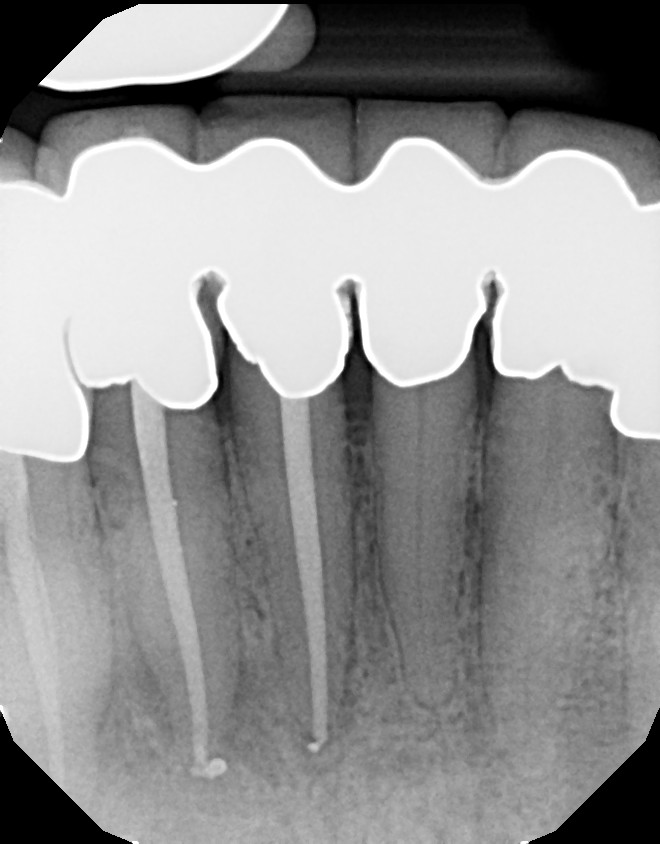

Long Island Endodontist shares his experience with root canal problems.

This is a multiple tooth / root issue that developed over time (4-5 years) under crowns where the nerves died and caused infection. After 3 months, bone regeneration (healing) occurred where infection was initially present. Endodontists (root canal specialists) are an important part of dental care for diagnosing and treating root issues.